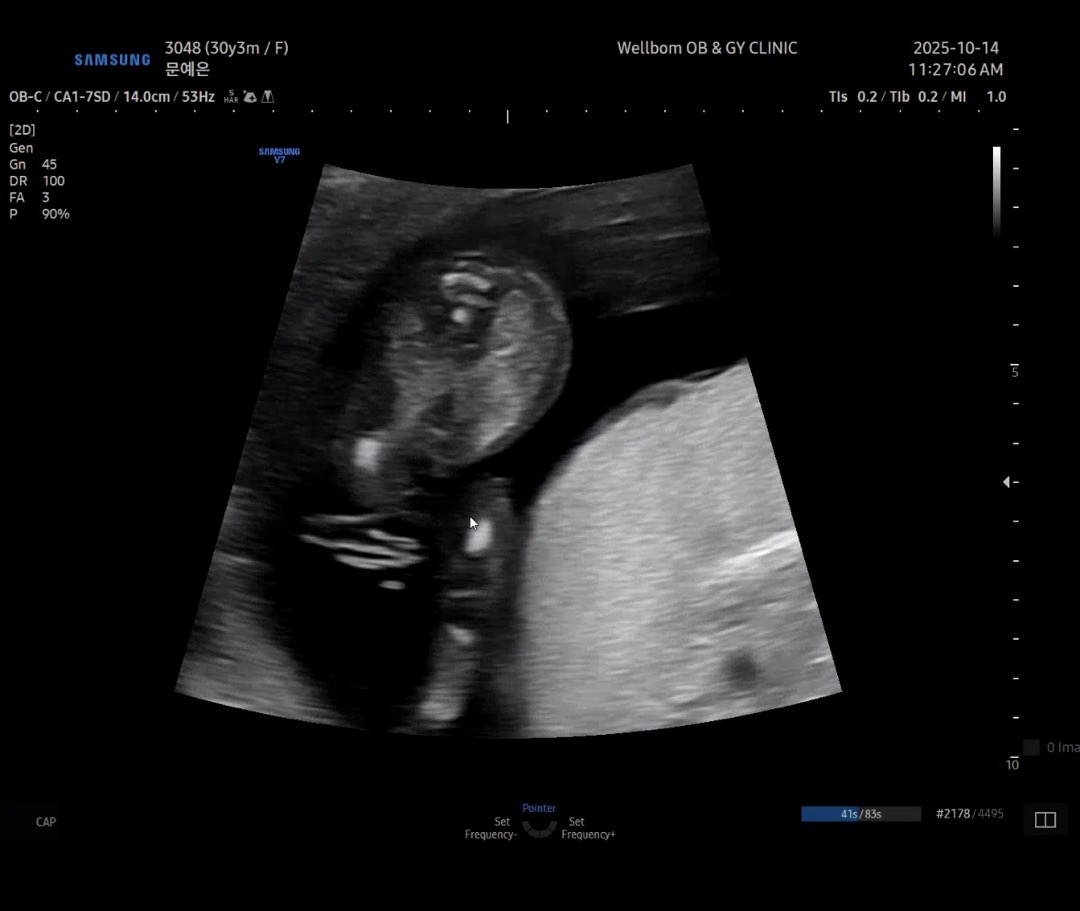

오늘 검사했는데 14주 3일이구요!! 아기가 커서 15주정도 되는데.. 선생님이 40% 딸이라는데 맞을까용?